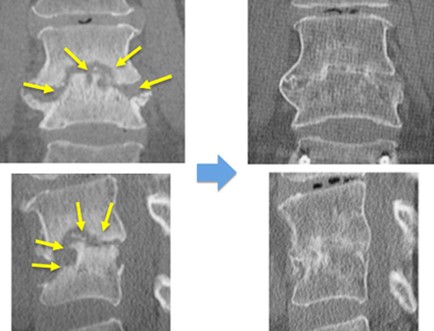

図 (上)第4番目、5番目の椎体が感染し、進行性の骨破壊と後弯変形を認めます。大きな切開を加えること無く、経皮的椎弓根スクリューを用いた特殊な方法で、脊椎を安定化しています。

(下、左)術前の進行性の骨破壊が見られましたが、(下、右)術後1年では良好な骨癒合が得られています。多くの場合、インプラントは一時的な固定として使用します。本症例では、約1年でインプラントを抜去しました。